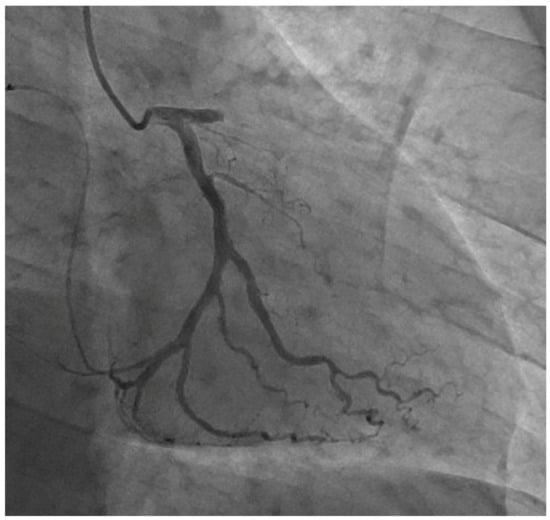

The baseline characteristics of our study subjects are presented in Table 1. The mean age at diagnosis was 49.3 years, and 60.8% were female. There were 9 (6.1%) patients with a history of previous myocardial infarction, 16 (10.8%) patients with a history of percutaneous coronary intervention, and 5 (3.4%) patients with a history of stroke. The initial LDL-C levels averaged 242.0 ± 97.9 mg/dL, which, when converted to treatment-naïve LDL-C levels, corresponded to 343.3 ± 140.9 mg/dL. When we categorized our study subjects according to the DLCN criteria, possible FH (score 3–5), probable FH (score 6–8), and definite FH (score > 8) were found in 27 (18.2%), 57 (38.5%), and 64 (43.2%), respectively. A representative coronary angiogram of a 42-year-old male with ST-segment elevation myocardial infarction is shown in Figure 2.

Figure 2. Representative coronary angiogram of a 42-year-old male with ST-segment elevation myocardial infarction.